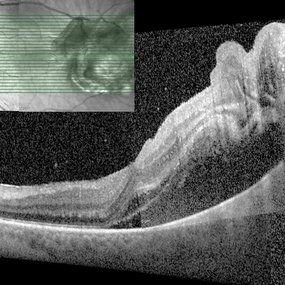

Iridociliary Medulloepithelioma

Feb 12 2020 by Scott D Walter, MD, MSc, FASRS

2-year-old male with a translucent, cystic, locally invasive iridociliary tumor consistent with medulloepithelioma (pre-treatment).

Condition/keywords: intraocular teratoid medulloepithelioma, iridociliary tumor